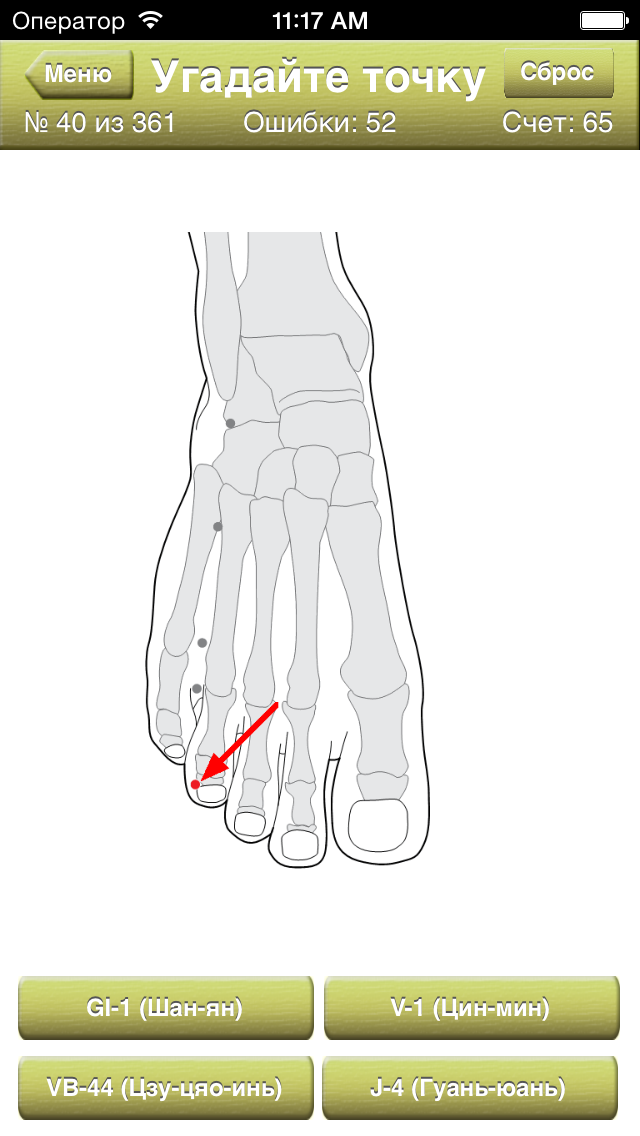

Скриншоты